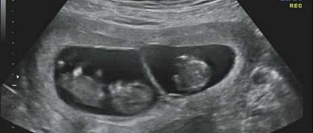

Двойня. Оптимальный срок для родов

По данным мета-анализа, который был опубликован онлайн 6 сентября 2016г. в журнале BMJ, для минимиза...

24.10.2016 35379 #беременность #двойня #многоплодная беременность #родоразрешение